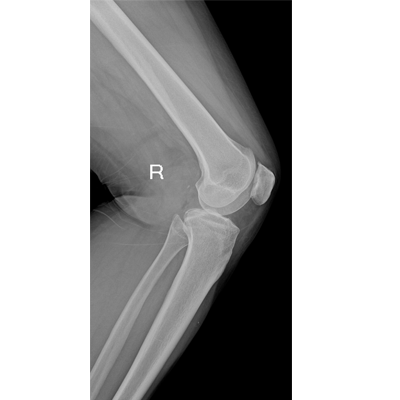

用于影像科、急診室、病房、ICU、手術(shù)室等多場景應(yīng)用。

● 數(shù)字化無線平板成像,操作簡便,成像質(zhì)量高